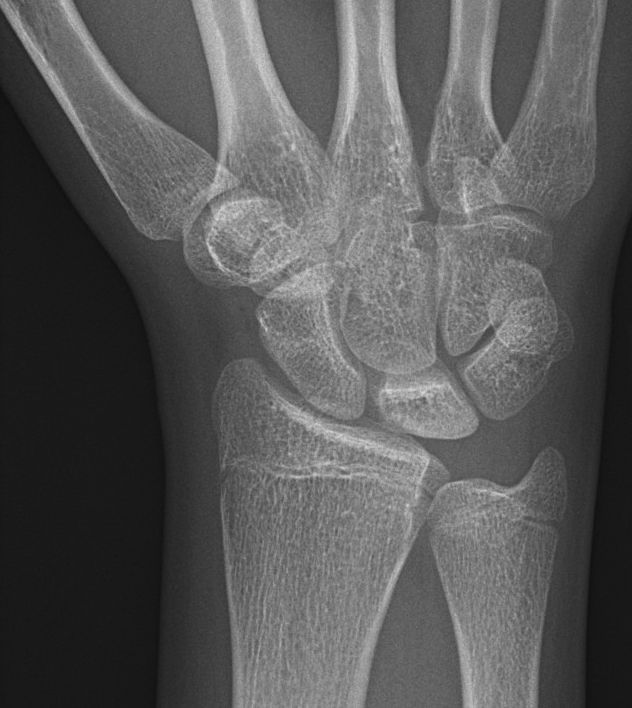

Stadium 2: Skleros av lunatum [1, 2]

Lunatummalaci stadium 2 med sklerotisk lunatum och ulnaminus